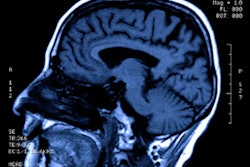

Insightec said it has received market approval for its Exablate 4000 (Neuro) platform from the National Health Surveillance Agency (ANVISA) in Brazil. Designed as a treatment for essential tremor and tremor-dominant Parkinson's Disease that has not responded to medications and neuropathic pain, Exablate Neuro provides MR-guided focused ultrasound to ablate tissue deep in the brain, according to the company.